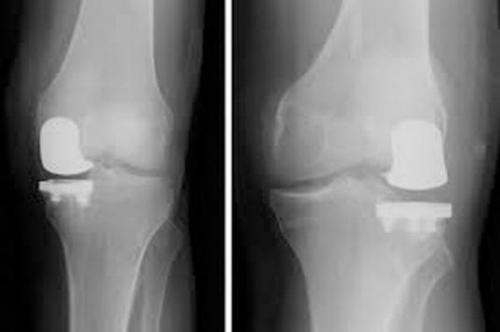

Artroza avansata, limitata la un singur compartiment poate fi tratata cu ajutorul protezei unicompartimentale de genunchi. In timpul procedurii, compartimentul afectat poate fi inlocuit cu un implant de plastic si metal. Cartilajul sanatos si osul, precum si toate ligamentele, vor fi pastrate.

1-pregatirea osului- in care ortopedul indeparteaza cartilajul si osul afectat din compartimentul genunchiului;

2- pozitionarea implantului de metal- in care osul si cartilajul afectat sunt inlocuite de un implant metalic pentru a recreea suprafata articulara a genunchiului. Aceste parti se fizeaza de os cu ajutorul cimentului medical.

3-Inserarea unui spatiator de plastic intre cele 2 componente metalice, pentru a creea un spatiu de alunecare a acestora.